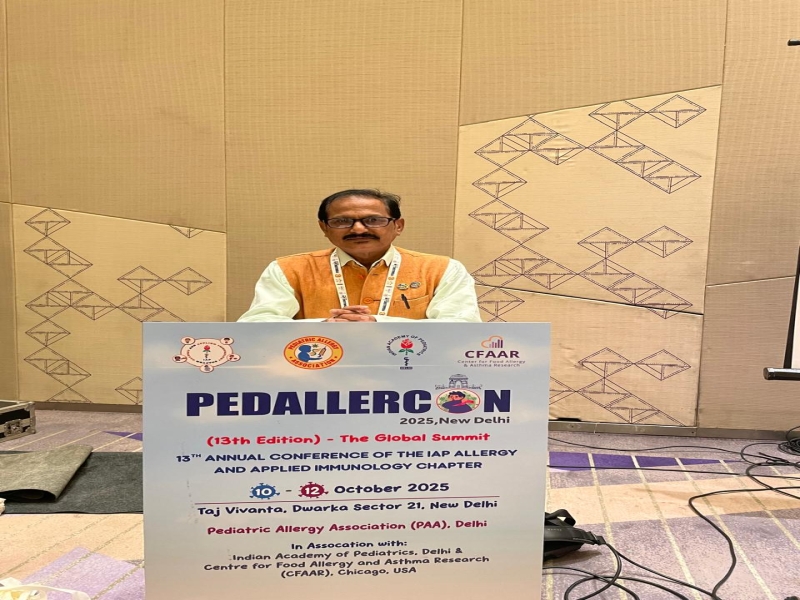

Welcome to the Bengal Allergy and Asthma Centre.We are certified specialists in Allergy and Clinical Immunology and have academic appointments . Our clinic provides comprehensive Allergy services for both children and adults.We manage the full range of allergic disorders, including food allergy, environmental allergy, anaphylaxis, stinging insect allergy, medication allergy, asthma, hives, and angioedema. Diagnostic allergy testing utilizes modern techniques that are gentle and well-tolerated. There is a strong focus on accurate diagnosis and personalized treatments based on medical evidence and experienced clinical judgment.